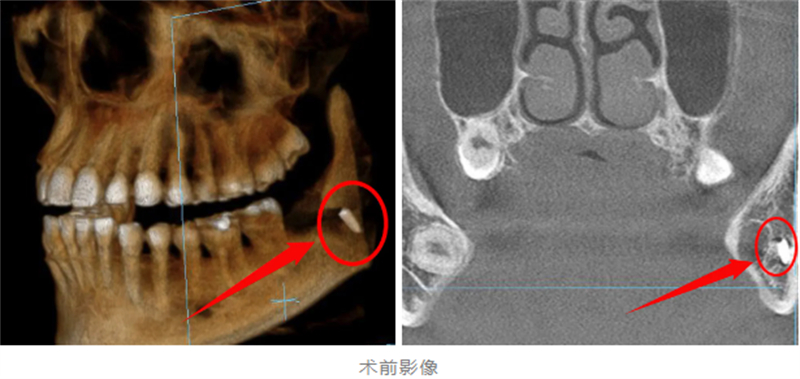

年僅28歲的王女士(化名)日前在某私人診所拔除下頜阻生智齒后,出現持續性口腔疼痛及異物感。察覺異常后,她緊急前往柳州市人民醫院口腔科就診。經CBCT(錐形束CT)影像檢查顯示,疑似拔牙器械尖端殘留于下頜骨內,且大部分嵌入下牙槽神經管區域,由于此處位置深在,鄰近重要血管、神經,手術取出難度極大。

據了解,此次患者殘留的器械尖端緊鄰下牙槽神經,若不及時取出,可能導致永久性神經損傷。而由于初次拔牙術后軟組織水腫、開口受限,二次手術操作空間極為狹小,對醫生的技術精度提出了極高要求。

最終,團隊憑借豐富的臨床經驗和默契配合,成功將一枚拔牙挺的斷端取出。術后患者生命體征平穩,疼痛癥狀明顯緩解,經影像檢查確認異物完整取出,目前已進入康復觀察階段。